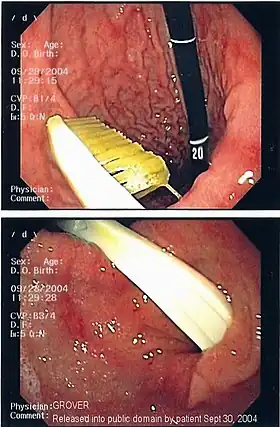

Commonly swallowed objects include coins, buttons, batteries, and small bones (such as fish bones),[1] but can include more complex objects, such as eyeglasses,[5] spoons,[6] and toothbrushes[5] (see image).

Once the foreign body has been identified with the gastroscope, various devices can be passed through the gastroscope to grasp or manipulate the foreign body. Devices used include forceps, which come in varying shapes, sizes and grips,[12] snares, and oval loops that can be retracted from outside the gastroscope to lasso objects,[13] as well as Roth baskets (mesh nets that can be closed to trap small objects),[14] and magnets placed at the end of the scope or at the end of orogastric tubes.[12][15] Some techniques have been described that use foley catheters to trap objects, or use two snares to orient foreign bodies.[6]